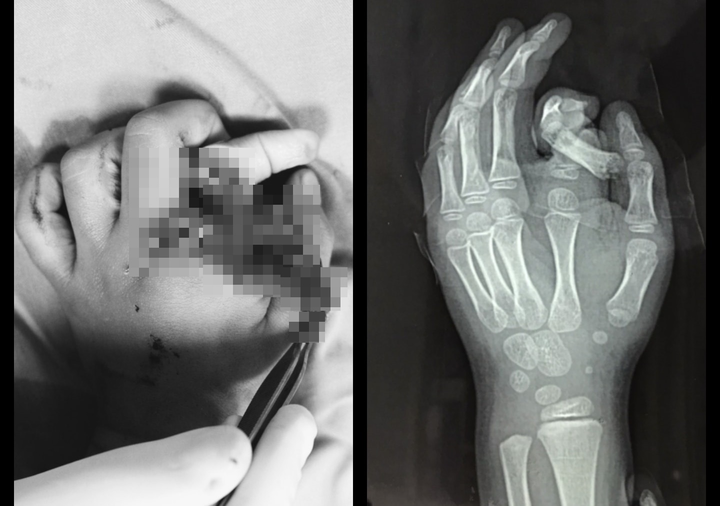

Bé trai nhập viện trong tình trạng ngón trỏ đứt rời, xoắn vặn, hệ thống thần kinh dây chằng bị nhổ bật một đoạn dài. Mặc dù các bác sĩ cố gắng để bảo tồn và nối ngón tay, nhưng do bị dập nát quá nặng và bệnh nhi còn nhỏ tuổi nên hiện tại chưa thể nối được.

Hình ảnh tổn thương ở tay của bệnh nhi. (Ảnh: BVCC).